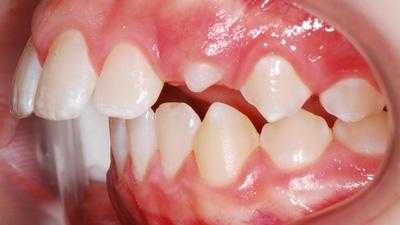

Внутриротовые признаки

В полости рта дистальный прикус определяется по выступающим вперед верхним фронтальным зубам. В норме, при ортогнатическом прикусе, верхние резцы перекрывают нижние примерно на 1/3. При дистальной патологии между верхними и нижними резцами образуется расстояние — «саггитальная щель».

- I подкласс — верхние резцы направлены вперед, иногда немного вверх. Для этого вида дистальной окклюзии характерная саггитальная щель.